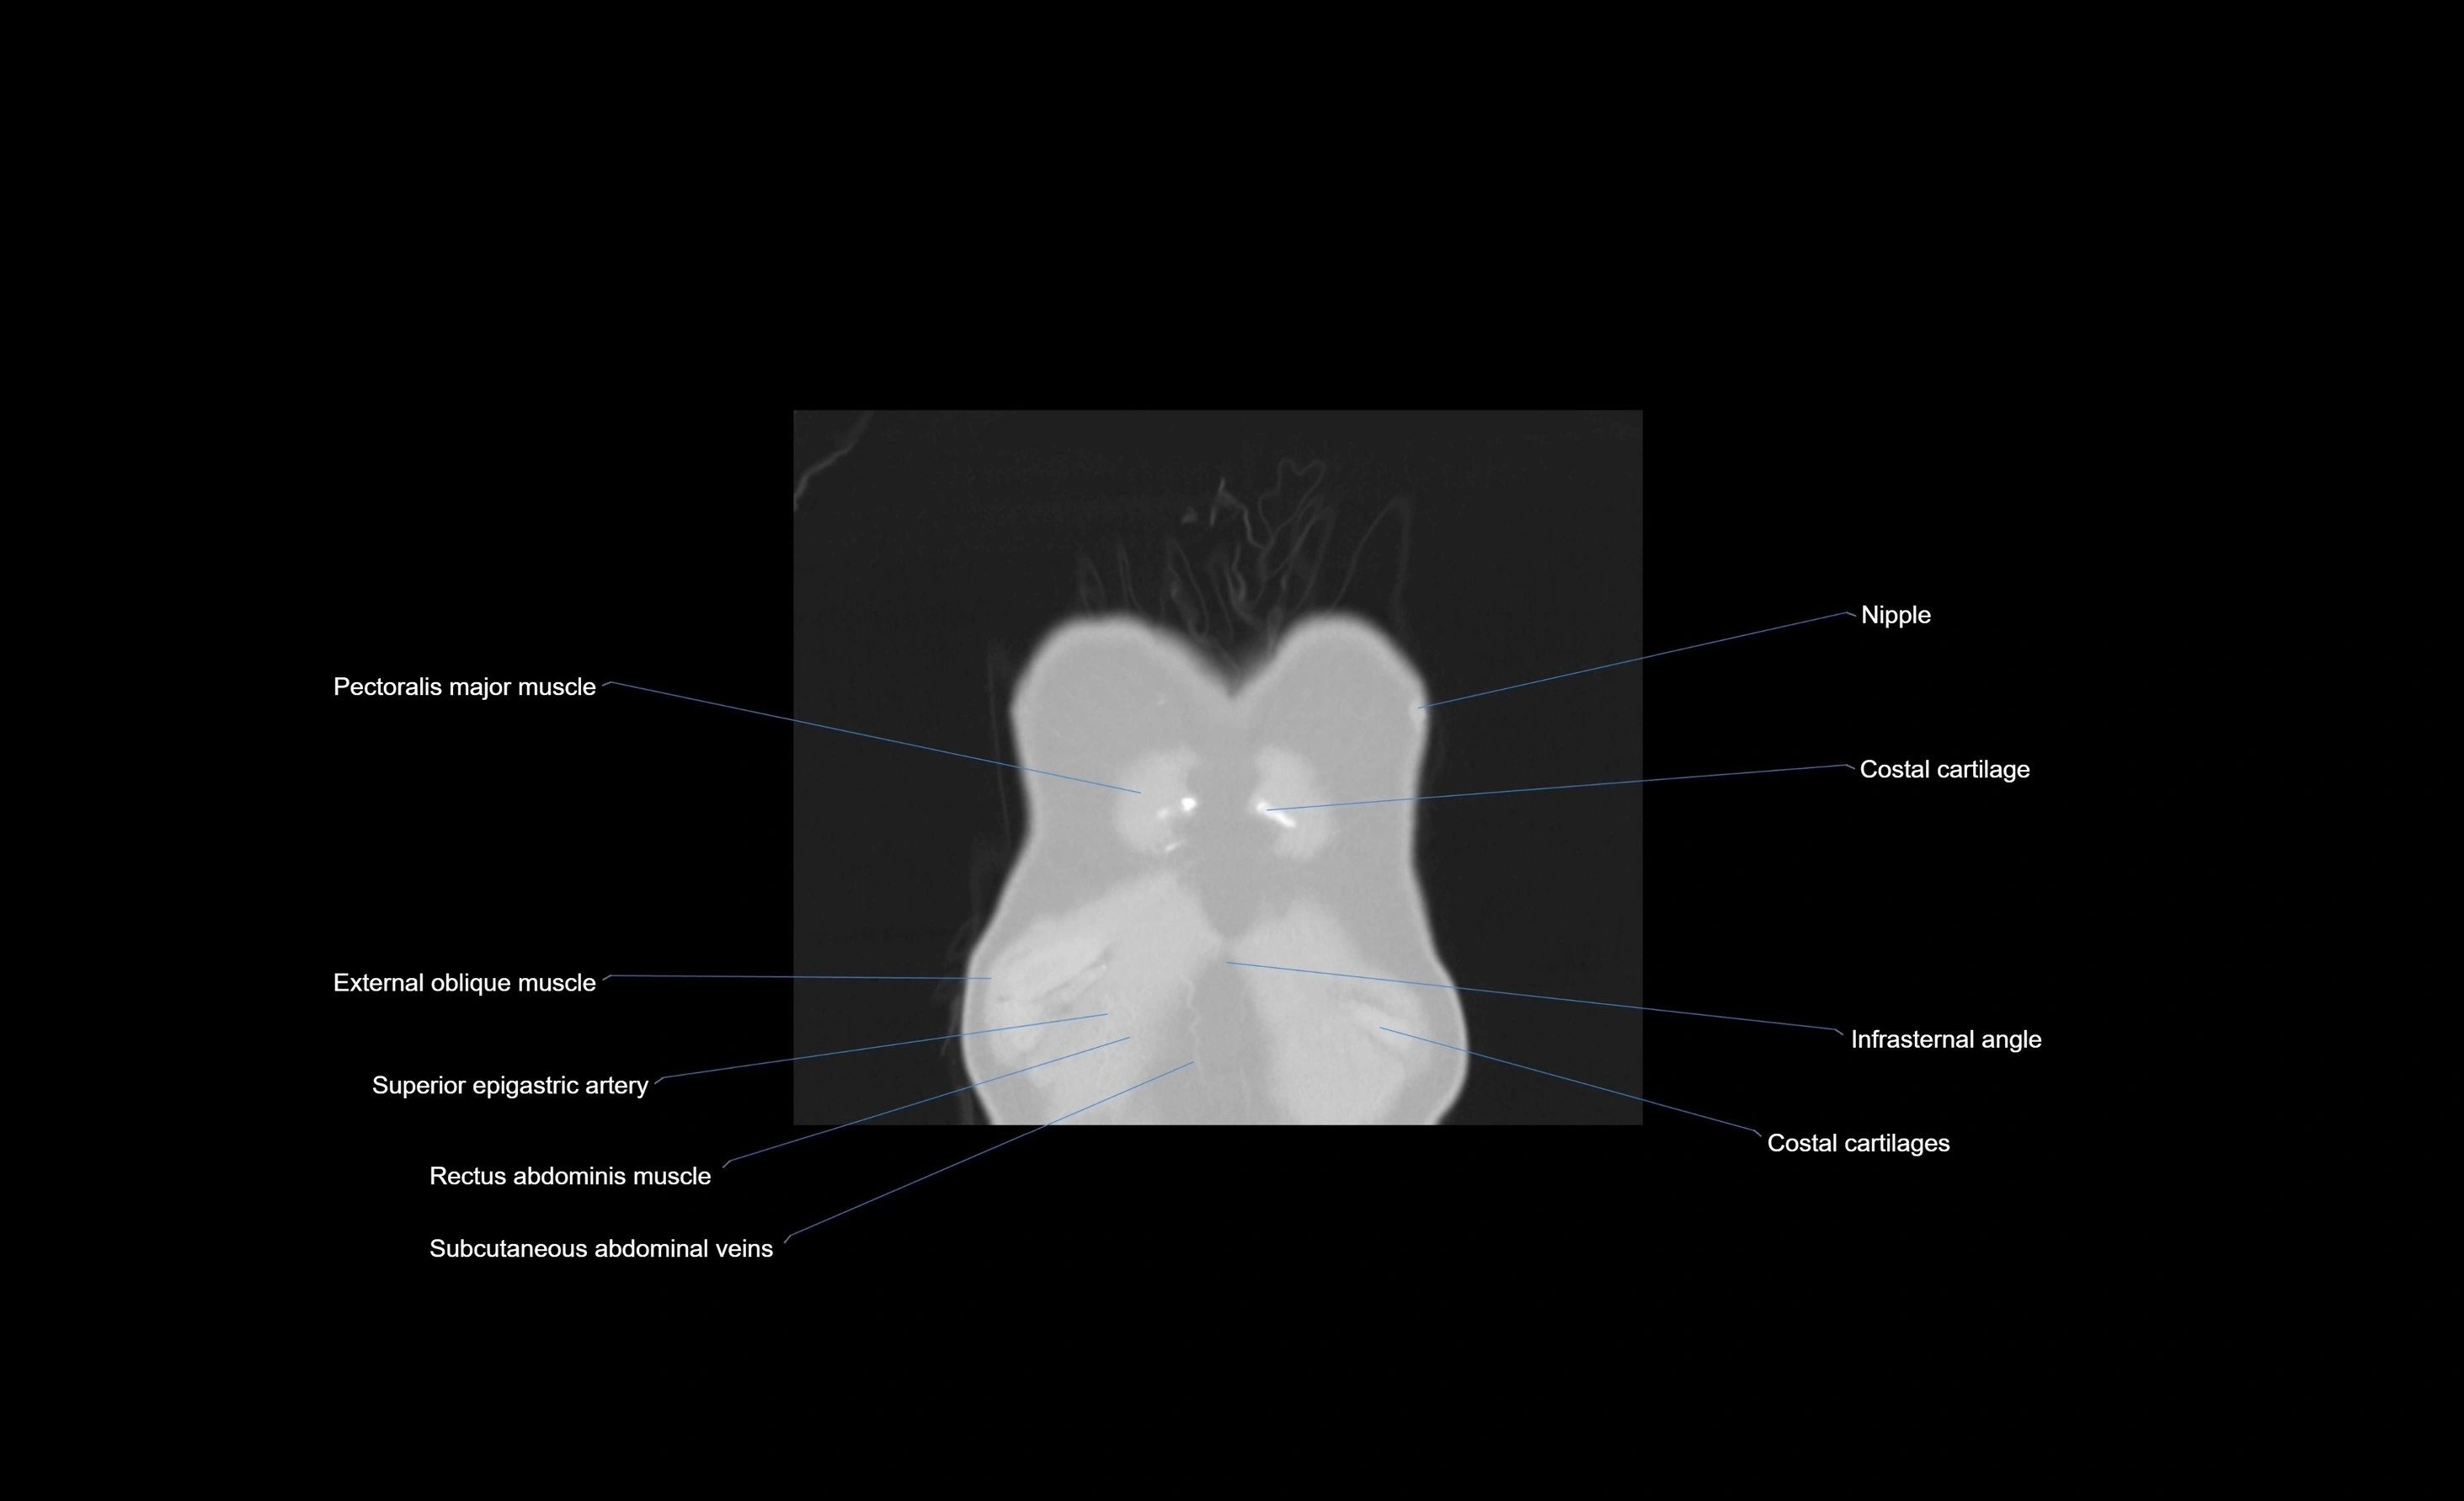

- Costal cartilages

- External oblique muscle

- Pectoralis major muscle

- Rectus abdominis muscle

- Superior epigastric artery